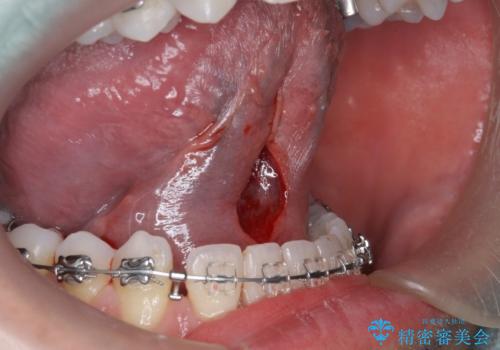

舌小帯の切除

- 他院で矯正治療をしているが、滑舌も気になるため舌小帯の切除を希望し来院されました。

手術自体は当日での処置が可能です。